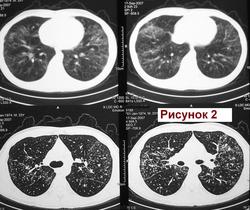

Муж.1974 г. р. Изменения впервые выявлены при проверочной флюорографии 2007 (Рис.1). Выполнена  КТ  легких (См фрагмент. Рис.2). Исчез. Продолжал работать. Не лечился. Пришел на обследование в 11.2011г. с жалобами на покашливание. Температура, кровь: норма. (Рис.3).  О какой патологии  легких можно думать? Я предположил саркоидоз. Специалистов по КТ очень прошу разъяснить рисунок 2. С уважением Nik.

Медиастинально-легочная форма саркоидоза.

Пациент обследован. Диагноз  саркоидоз органов дыхания  подтвержден. Спасибо. С уважением к Вам Nikolas